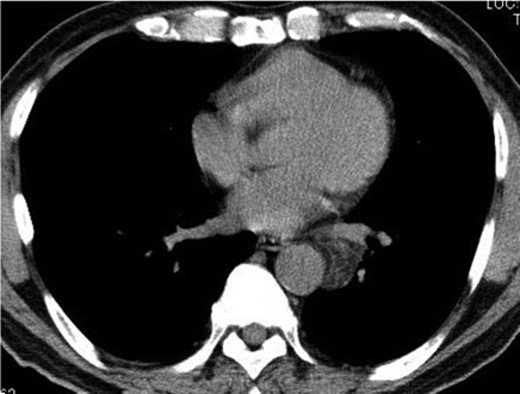

A 74-year-old man was referred to our hospital after a left middle and posterior mediastinal tumor was detected on computed tomography (CT) performed as an examination for dry cough in other hospital. CT about 2 years earlier had shown a 3.2 × 2.4-cm lipomatous tumor at the left hilum adjacent to the left lower pulmonary vein (Fig. 1), and that lipomatous tumor was considered the origin of the present mediastinal tumor. Contrast-enhanced CT performed in our hospital showed a heterogeneous tumor, displacing the left lower lobe of the lung, and measuring 10 × 7.4 × 6 cm on horizontal and coronal sections (Fig. 2A and B). Magnetic resonance imaging showed a hyperintense marginal region with central hypointensity on T1-weighted imaging, and heterogeneously high intensity in the whole tumor on T2-weighted imaging. We scheduled surgical resection, and the patient was admitted to our hospital 3 weeks after the first visit. Chest radiography showed rapid growth of the left intrathoracic tumor (Fig. 3A and B), and CT revealed a tumor measuring 11.4 × 8 × 6.2 cm without pleural effusion or hemothorax.

Contrast-enhanced CT of the chest shows an oval, smooth-shaped, heterogeneous tumor displacing the left lower lobe of the lung, measuring 10 × 7.4 × 6 cm on horizontal (A) and coronal (B) sections without pleural effusion or hemothorax.